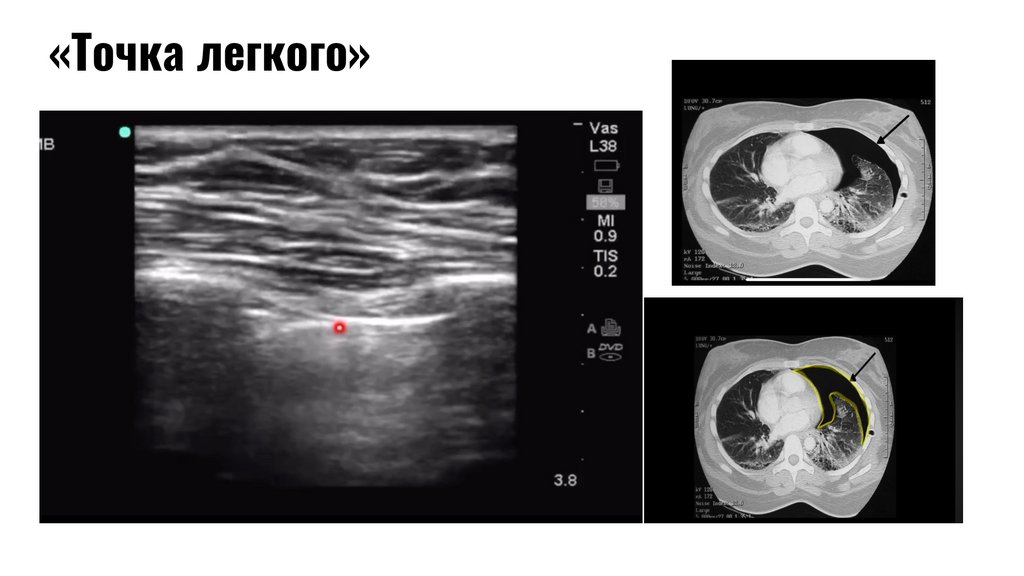

«Точка

легкого»

Точка лёгкого